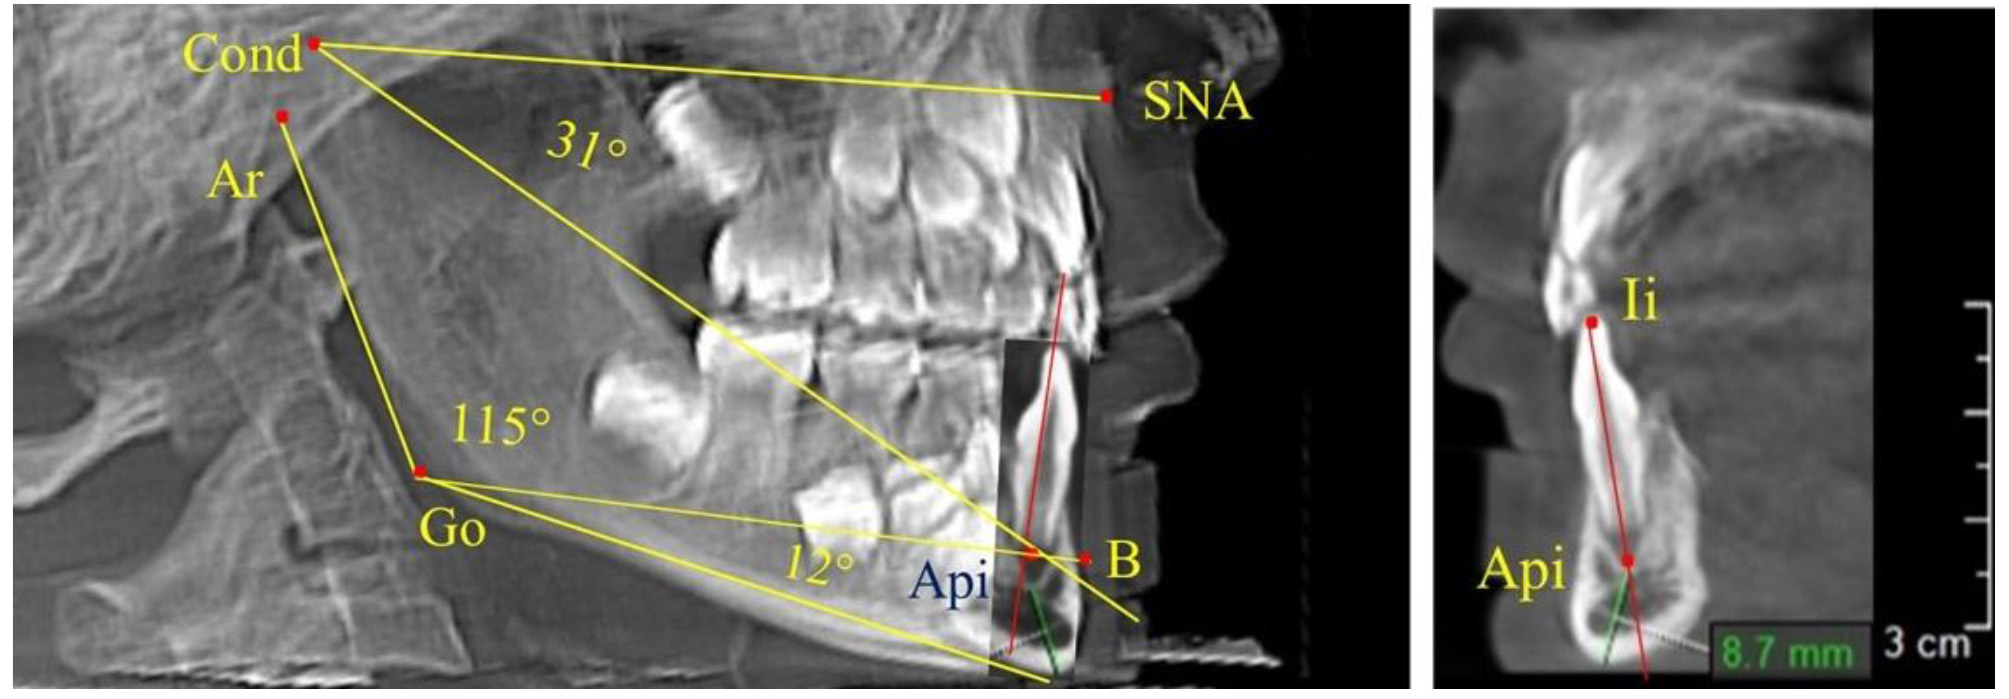

Особенность анализа телерентгенограммы в периоде сменного прикуса заключалась в том, что наслоение зачатков постоянных зубов затрудняло определение апикальной точки нижнего резца. В подобных случаях использовали метод совмещенного анализа телерентгенограммы с фрагментом томограммы, на котором, также как и на телерентгенограмме, определяли положение резцовой и апикальной точек с построением условной вертикали, которая служила ориентиром для совмещения фрагментов (рис. 2).

Рис. 2. Особенности совмещения телерентгенограммы с фрагментом томограммы в сменном прикусе